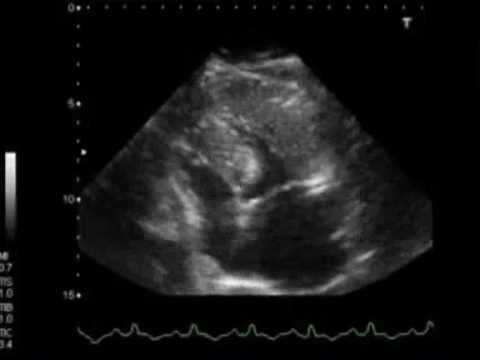

2. Acute Coronary Syndrome with Severe LV Dysfunction, by Dr AM. Thirugnanam, :

how to cure lv dysfunction

3. Diastolic function: An introduction :

4. 4C. Chronic LV dysfunction? Compare with 4A-E (WINFOCUS, CC ECHO Course, by Gabriele Via) :

15. ICU echo course LV systolic Function :